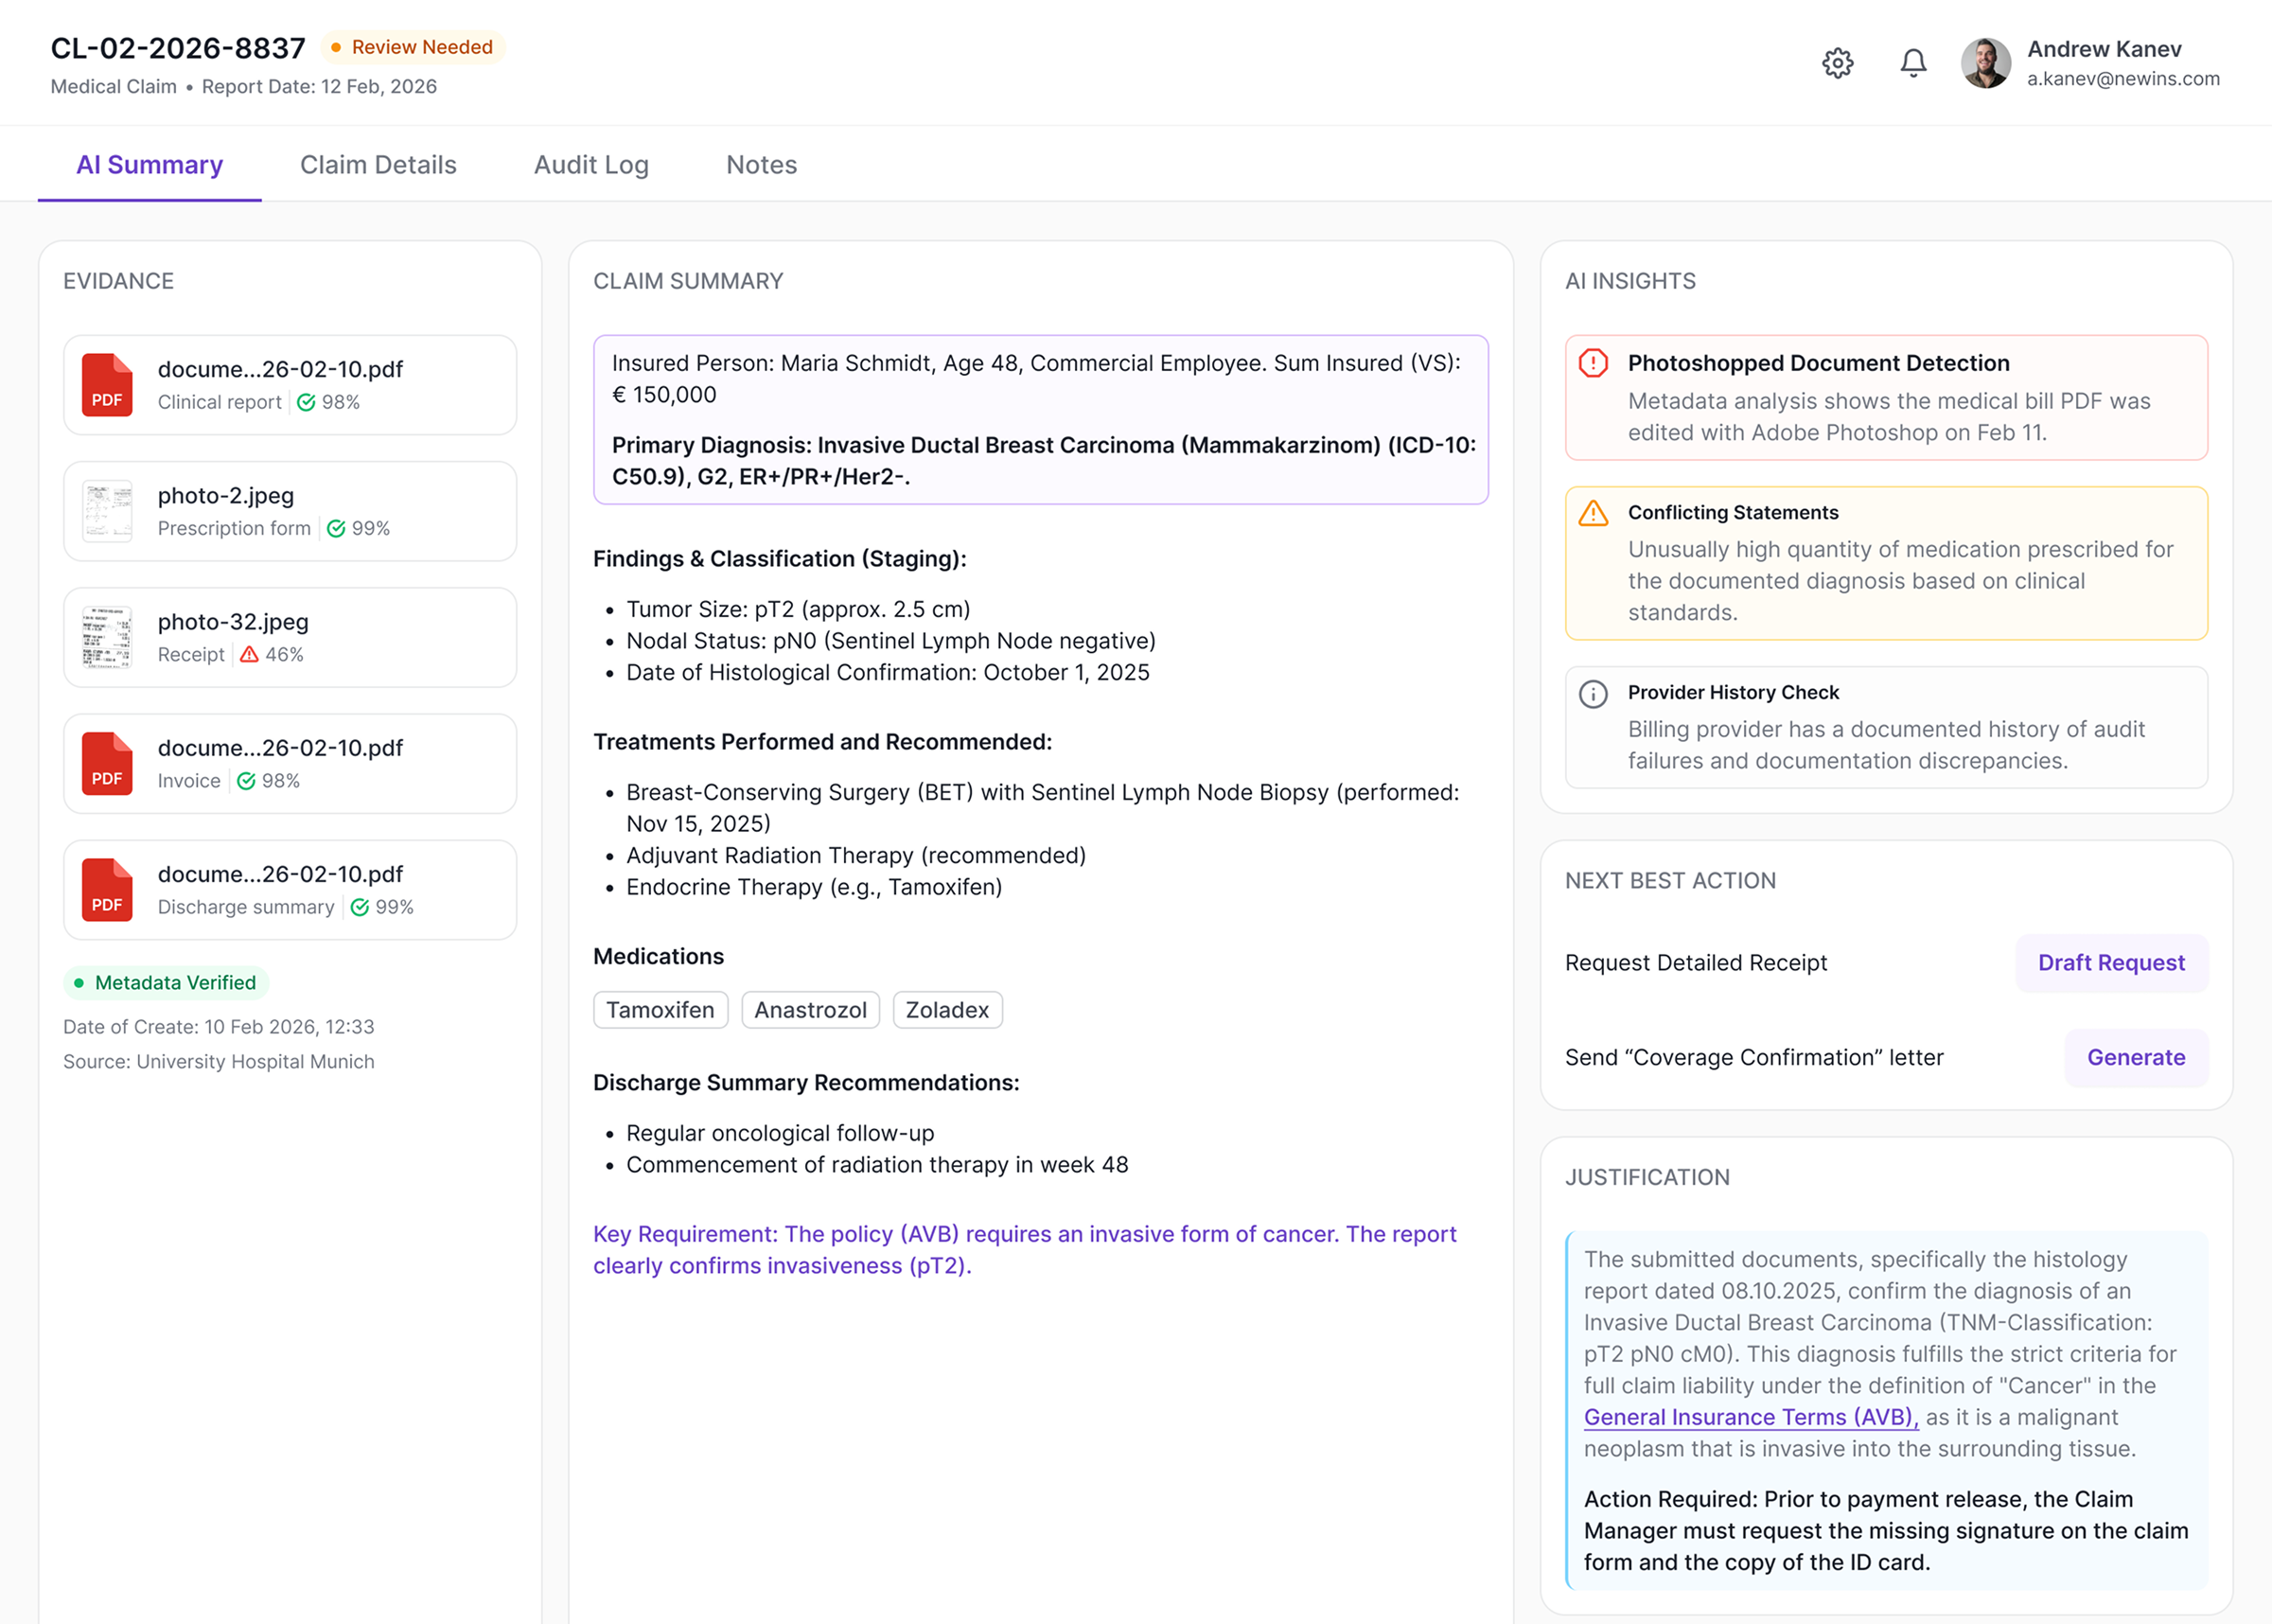

USE CASES

“Underwriting optimization through AI-supported decision models.”

PROVEN IMPACT

Results backed by data

Proven results from insurers who already use K2G AI Agents to transform their pricing, risk management and portfolio growth.

Market Share

Leverage alternative data and real-time monitoring to capture new opportunities.

Time-to-Analysis

Automate repetitive actuarial and underwriting tasks to accelerate decision-making.

Pricing Accuracy

Achieve higher precision in risk-based pricing and reduce financial exposure.